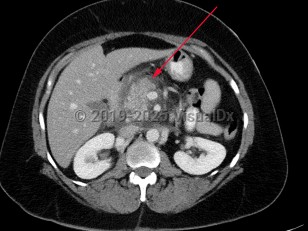

Chest pain, Pleural effusion, 50-59 year old Female

Spontaneous rupture of esophagus

Aortic dissectionAortic dissection

Aortic intramural hematoma